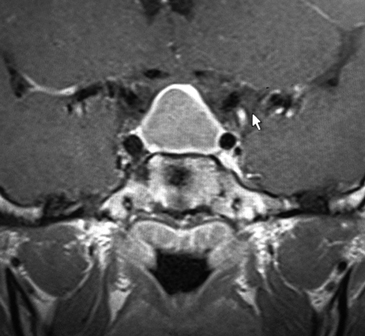

Se completa estudio por imágenes con RM silla turca informada como lesión quística selar. Posteriormente se revisan las imágenes y destaca una lesión quística con realce periférico “en anillo” (Figura 1).

Figura 1. RM selar con realce periférico "en anillo", característico del absceso hipofisiario.

Imagenológicamente habitualmente aparece como una lesión selar quística, con realce periférico en anillo tras la administración del contraste intravenoso en RM, como se observó en nuestro caso al revisar las imágenes2,5.

El diagnóstico preoperatorio de los abscesos hipofisiarios es difícil debido a su clínica insidiosa y hallazgos radiológicos poco específicos. Se debe sospechar ante un paciente con una masa selar quística con realce en anillo, sobre todo si se asocia a clínica infecciosa y/o diabetes insípida e hipopituitarismo.